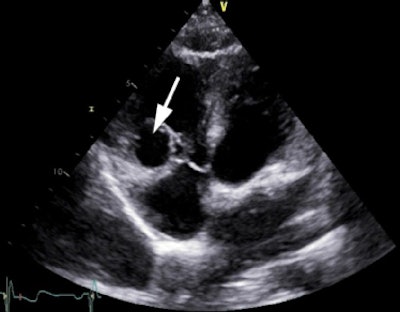

Transthoracic echocardiography (modified four-chamber view) in a 42-year-old female with atypical chest pain and stress electrocardiogram (ECG), suggesting myocardial ischemia. The arrow points at an unusual structure in the right ventricle.

By Drs. Bogdan Popescu and Roxana Enache, University of Medicine and Pharmacy "Carol Davila" - Euroecolab, Institute of Cardiovascular Diseases "Prof. Dr. C. C. Iliescu," Bucharest, Romania.